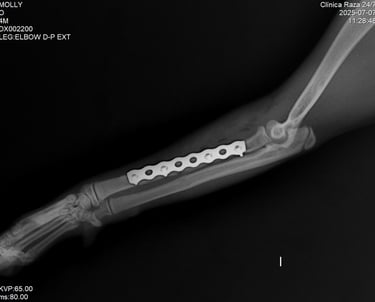

Un sistema de placa bloqueada es una técnica avanzada de fijación interna en la que los tornillos se bloquean directamente a la placa, formando una estructura rígida y estable.

A diferencia de las placas convencionales, este sistema no depende de la compresión contra el hueso, lo que permite:

Fijación de la placa al hueso

La placa se posiciona sobre el hueso afectado, adaptándose a su anatomía sin necesidad de comprimirlo directamente.

Inserción de tornillos bloqueados

Los tornillos se introducen atravesando la placa y se enroscan en ella, quedando firmemente anclados tanto al hueso como a la placa.

Formación de un sistema rígido

Al bloquearse los tornillos con la placa, se crea una estructura estable tipo “armazón” que no depende de la presión sobre el hueso.

Estabilización y cicatrización ósea

El sistema mantiene los fragmentos óseos alineados, permitiendo una adecuada recuperación y favoreciendo la cicatrización.

Los sistemas de placa bloqueada ofrecen ventajas significativas frente a métodos tradicionales, ya que combinan estabilidad mecánica con un enfoque más biológico de la reparación ósea.

Mayor estabilidad

La fijación entre tornillo y placa crea una estructura rígida que mantiene los fragmentos óseos alineados incluso en fracturas complejas.